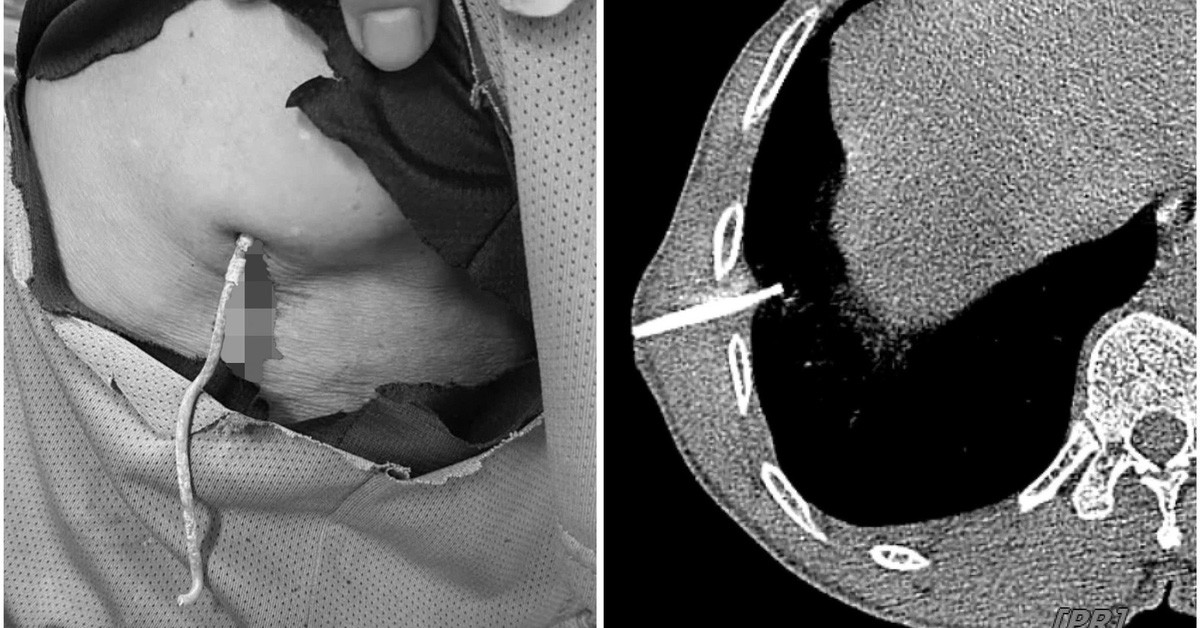

| Di vật được xác định là kẽm thường được làm hàng rào găm vào xuyên thủng phổi phải người bệnh. Ảnh: BVCC |